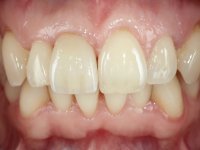

The patient did not like the upper right central incisor. I wanted to improve the smile because the “front tooth was dark and narrow”.

Female patient, 41 years old, non-smoker. It presented tooth 11 with a composite resin restoration, of great extension, very infiltrated and aesthetically poor. In the imaging exam, it was verified that the endodontic treatment was not technically satisfactory, but asymptomatic for almost 20 years. Between teeth 11 and 12 it showed a periodontal pocket certainly related to the non-adapted restoration. Tooth 11 showed a reduced mesiodistal diameter in relation to the symmetrical one. Medium thickness periodontal with satisfactory oral hygiene.

The treatment began with the placement of an intraradicular post and the creation of a new composite resin restoration. This procedure was performed with a surgical approach that allowed the remaining margins to be completely exposed, which were shown to be at a very infra-gingival level. Simultaneously, the periodontal pocket was curetted and root scaling and root planning of adjacent teeth were performed. Two months after this first intervention, the making of the crown began. A pre-print on silicone was performed to make a temporary crown with dual-cured composite resin. Gingival retraction was performed using the technique of kaolin paste compressed by the provisional crown. The impression was made using the double-mix technique with double viscosity with quick-setting silicone. In the laboratory, a crown with a ceramic-coated Zr infrastructure was made. The crown slightly overlapped tooth 12, allowing a dimensionally mimicry of the symmetrical tooth. Its fit was confirmed and approved by the patient; it was definitively cemented with resin-reinforced glass ionomer cement.